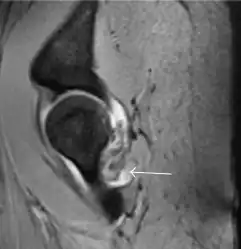

Most of the angles and measurements described in the plain radiograph section can be accurately reproduced on MRI. In addition, the superiority of MRI resolution with intra-articular contrast allows detection of labral and chondral abnormalities that may influence the choice of medical, percutaneous, or surgical management (Figure 9).[1]

Figure 9:

-

Sagittal T1 weighted image showing anterosuperior labral tear.[1] -

Sagittal T1 weighted image showing chondral lesion.[1] -

Sagittal CT-arthrography showing posteroinferior chondral injury.[1] -

Coronal CT-arthrography (d) showing ligamentum teres tear.[1]

MR arthrography has proven superior in accuracy when compared to native MR imaging. It is considered the best technique to assess the labrum. Knowledge of the normal variable morphology of the labrum helps to differentiate tears from normal variants. A triangular shape is most commonly seen in 66% of asymptomatic volunteers, but round, flattened, and absent labra can also be found in asymptomatic populations. MR arthrography has demonstrated sensitivity over 90% and specificity close to 100% in detecting labral tears. Loose bodies are demonstrated as filling defects surrounded by the hyperintense gadolinium.[1]

Association between labral tears and chondral damage has been demonstrated. This underscores the interaction between cartilage and labrum damage in the progression of osteoarthritis. Chondral damage to the posteroinferior part of the acetabulum as a contrecoup lesion occurs in approximately one-third of pincer cases secondary to persistent abutment on the anterior part of the joint leading to a slight posteroinferior subluxation. This is considered a bad prognosis sign.[1]

MR arthrography can also demonstrate ligamentum teres rupture or capsular laxity, which are debated causes of microinstability of the hip. Elongation of the capsule or injury to the iliofemoral ligament or labrum may be secondary to microtrauma in athletes. MR can demonstrate abnormalities in these cases, such as increased joint volume or a ligamentum teres tear (Figure 9).[1]